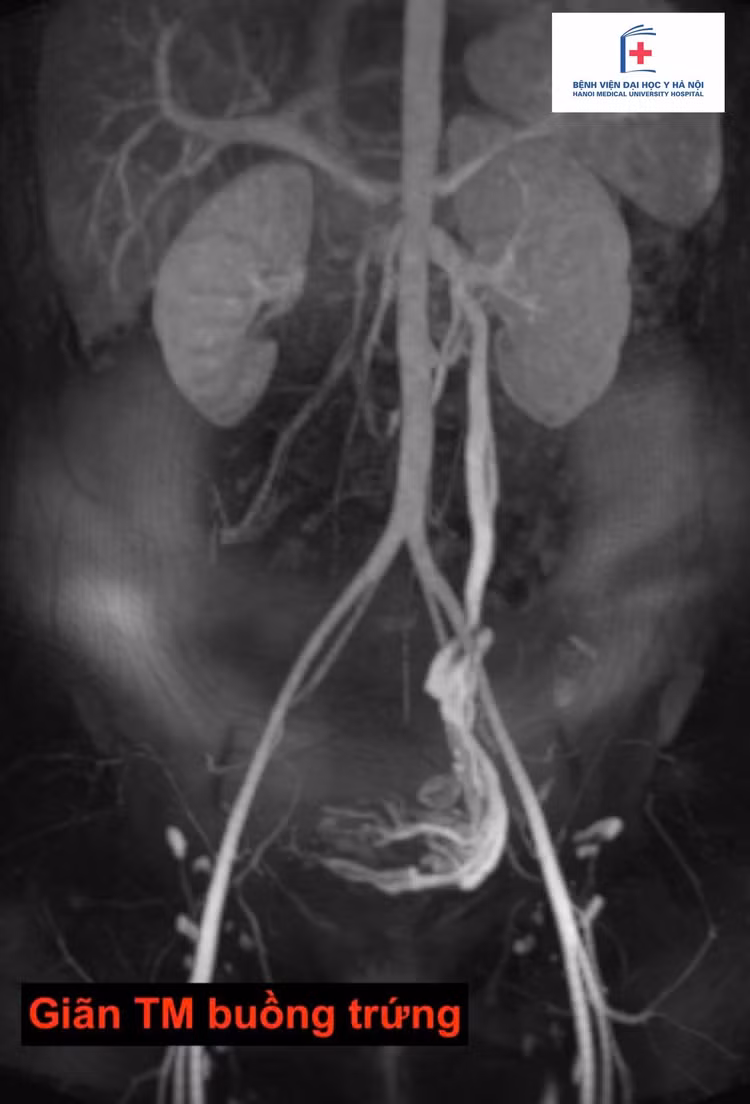

gian-tinh-mach-buong-trung.jpg

Ảnh BSCC

Sau khi chuyển đến chuyên khoa Điện quang can thiệp tại Bệnh viện Đại học Y Hà Nội, người bệnh được chẩn đoán mắc Hội chứng xung huyết vùng chậu (Pelvic Congestion Syndrome) - một bệnh lý do giãn tĩnh mạch buồng trứng, thường bị bỏ sót do biểu hiện không đặc hiệu.

Chẩn đoán được xác định thông qua siêu âm ổ bụng và chụp CT có tiêm thuốc cản quang. Các bác sĩ đã giải thích, tư vấn cho người bệnh về điều trị bằng phương pháp nút mạch qua da - sử dụng dụng cụ can thiệp để bít tắc các tĩnh mạch giãn bất thường, ngăn dòng máu trào ngược gây đau. Sau can thiệp, triệu chứng đau giảm rõ rệt, người bệnh phục hồi nhanh chóng.